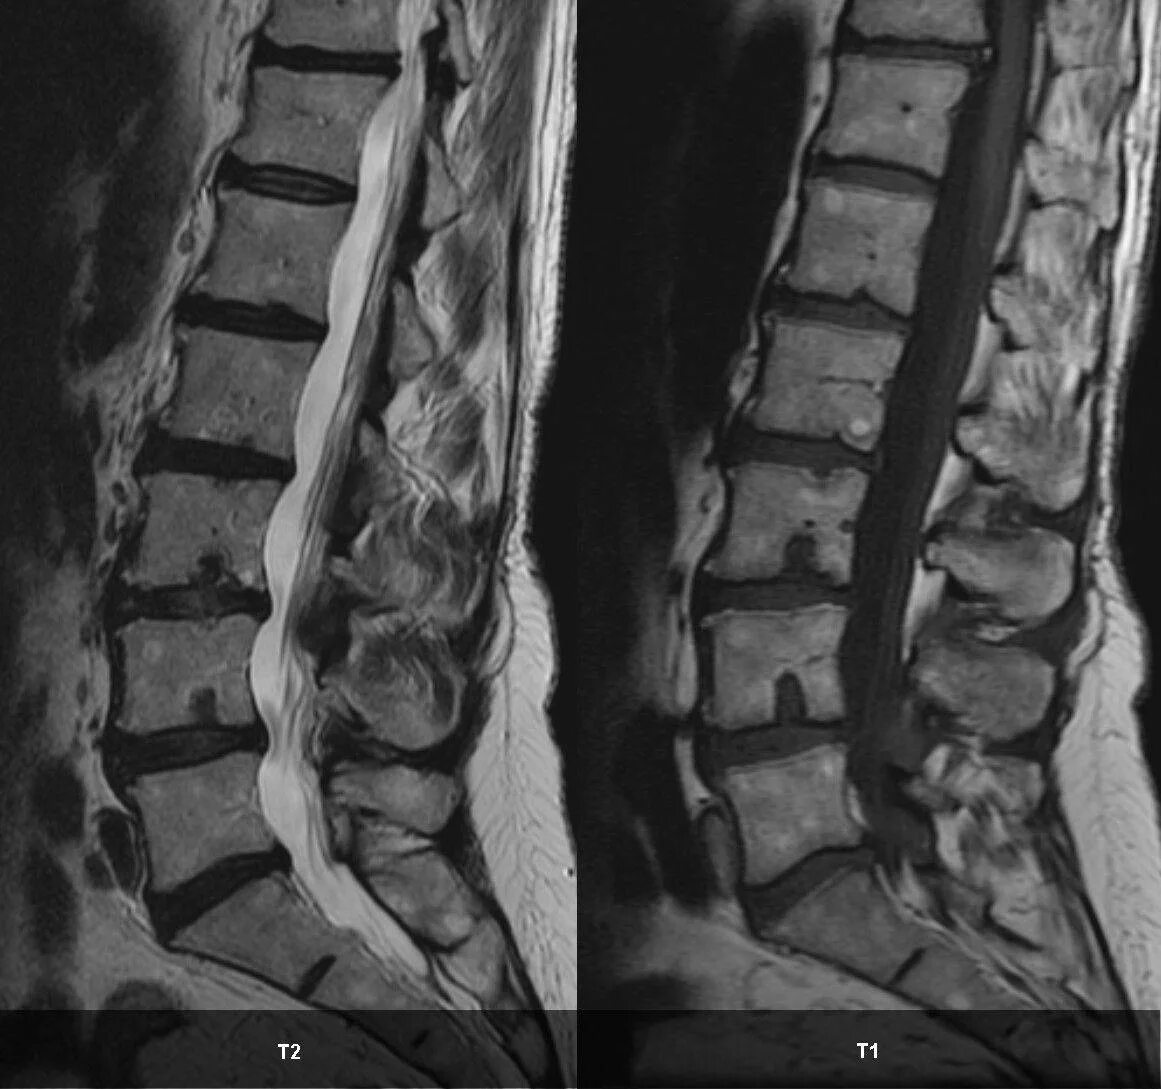

Что значит грыжа шморля